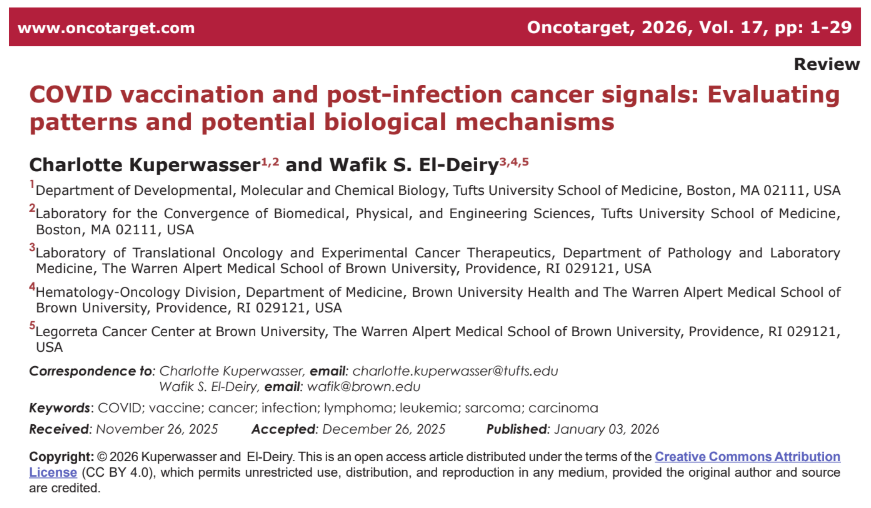

De beschreven kankertypen zijn divers. Het gaat onder meer om hematologische maligniteiten, zoals non-Hodgkinlymfomen, cutane lymfomen en leukemie, maar ook om solide tumoren, waaronder borst-, long-, pancreas- en huidkanker, sarcomen en glioblastomen. Over de verschillende publicaties heen signaleren de auteurs enkele terugkerende klinische patronen, waaronder een opvallend snelle tumorprogressie en herhaling of heractivatie van eerder stabiele ziektebeelden. Ook worden atypische histopathologische kenmerken genoemd, zoals afwijkingen nabij vaccinatieplaatsen of regionale lymfeklieren.